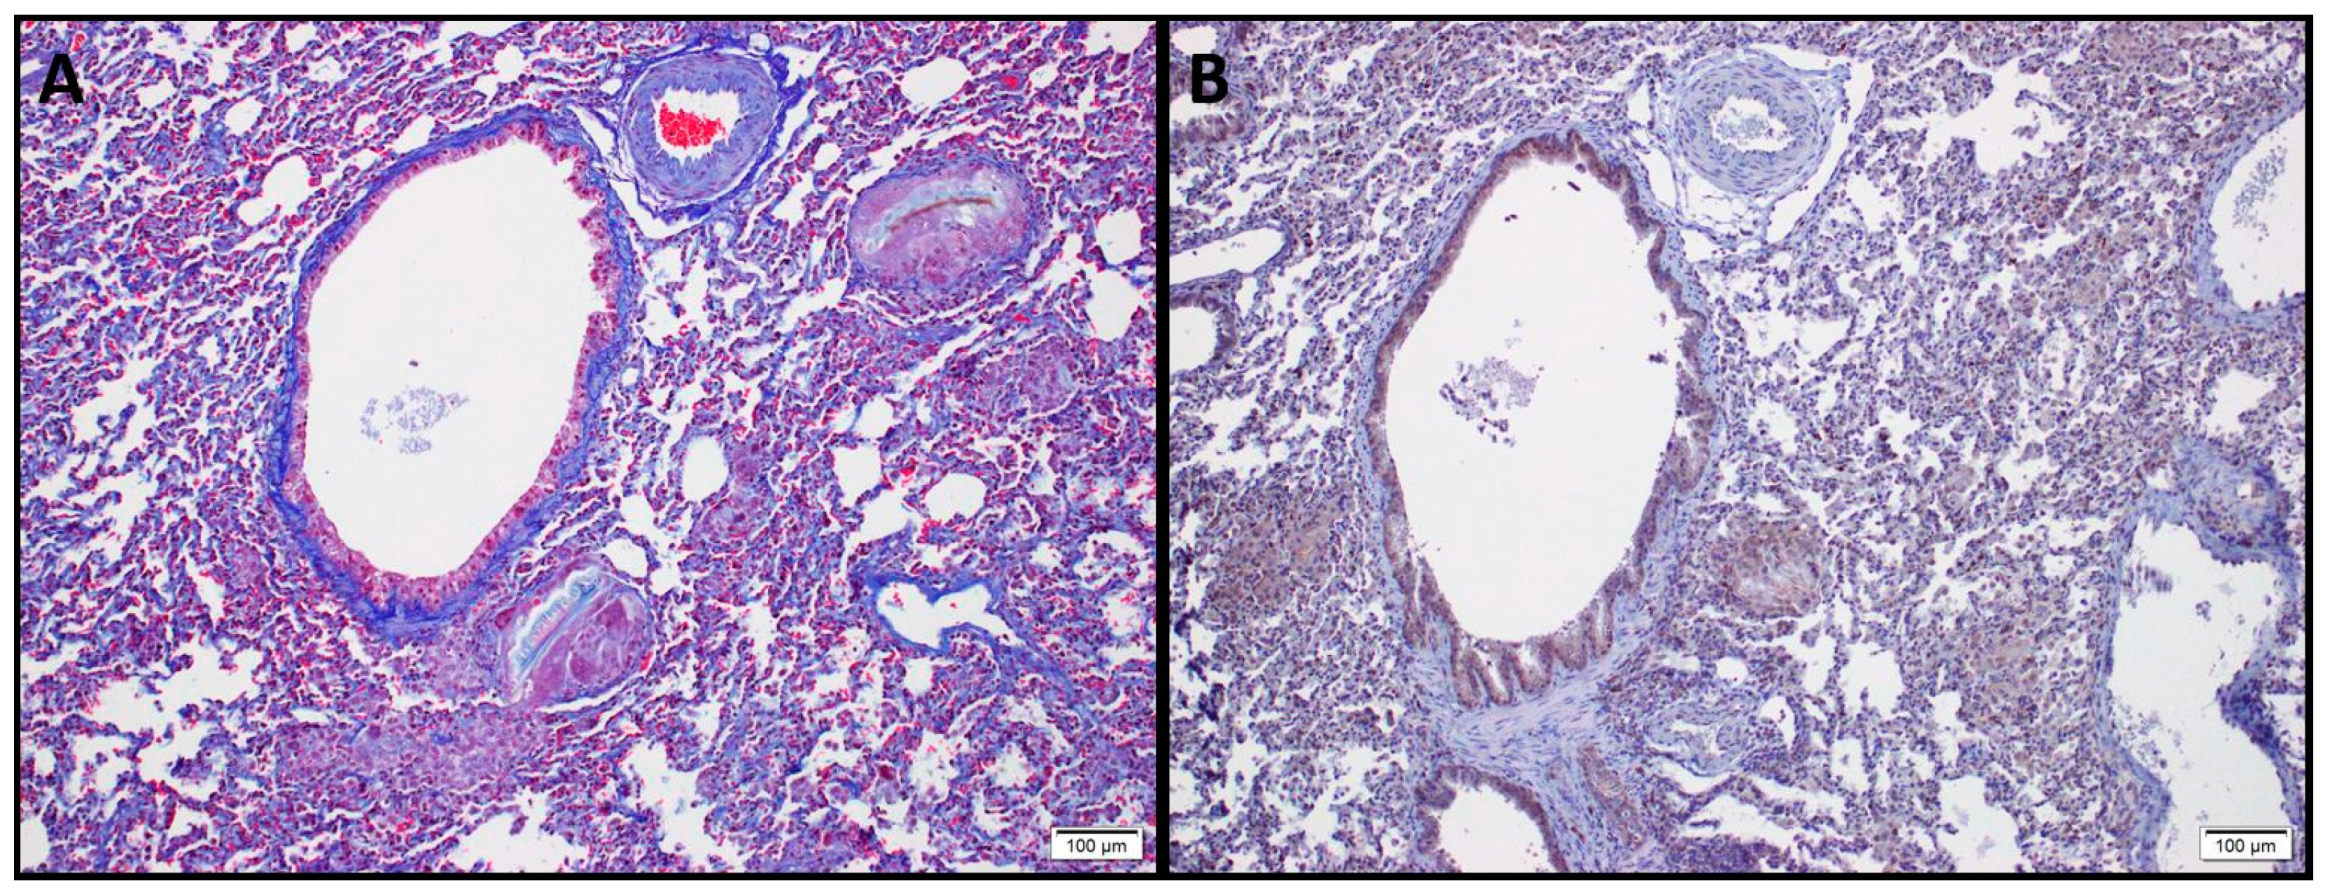

Figure 3.

Sections from rabbit lungs 60 days after intratracheal instillation of 0.1 N–hydrochloric acid. (A) Masson’s Trichrome staining depicting fibrotic lesions, loss of alveolar architecture, peribronchial, and perivascular collagen deposition. (B) HSP90β immunohistostaining of the same section displaying upregulation of HSP90β (in brown) within the fibrotic tissue and in peribronchial regions.

Strong expression of both HSP90α and HSP90β was observed in abnormal bronchiolar structures overlying fibroblast foci, as well as in hyperplastic bronchioles of IPF lungs. Hyperplastic type-II alveolar epithelial cells (AECII) near areas of dense fibrosis displayed robust immunostaining of HSP90β in IPF lungs compared to healthy donors, whereas HSP90α was absent in AECII. Smooth muscle cells located in the wall of bronchioles showed expression of HSP90α and α-SMA, but not of HSP90β [65]. Collagen type I secretion likely depends on the activity of HSP90 chaperones, even though such chaperone cannot directly engage nascent collagen molecules, but in addition to promoting TGF-β signaling, it could influence collagen-I secretion via interactions with cytosolic components of the secretory pathway [77]. Taken together these data suggest how HSP90 is involved in TGF-β receptor stabilization, its Smad-dependent and Smad-independent signaling cascade and could influence Collagen I secretion, representing an interesting target of new anti-fibrotic therapies (Figure 4).